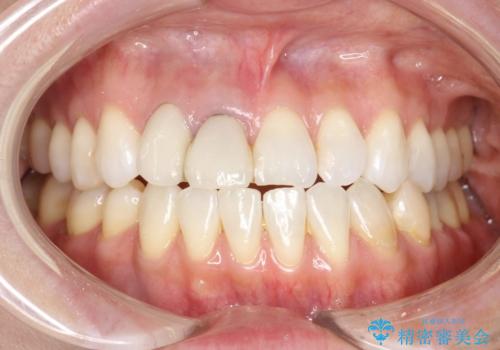

[フルジルコニアクラウン] 老朽化した銀歯を白く